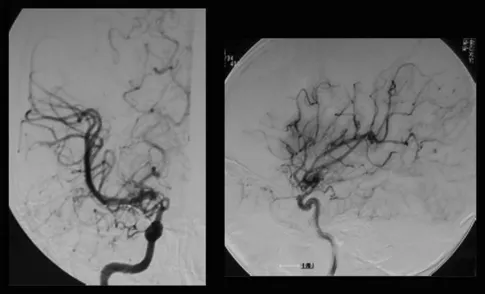

图片一名8岁烟雾病患儿影像,形如烟雾

MRI没有发现脑卒中病变,但基底节有多个血流空洞。MRA显示右颅内颈内动脉末端狭窄,左颈内动脉造影显示颈内动脉无狭窄,右大脑前动脉由左大脑前动脉经前连合动脉供血。右颈内动脉造影显示颈内动脉末端狭窄,大脑前动脉缺失,大脑中动脉较左动脉扩张,烟雾血管在颈内动脉顶部形成(图1)。Suzuki期为II期或介于II期和III期之间的过渡期。氙-CT灌注成像技术Xe-CT静息时及负荷时对比,显示右侧大脑中动脉区脑血管反应为14.8%,与左侧相比,右侧大脑中动脉区域的血供摄取没有明显减少(图2)。

图1:术前右颈血管造影显示,在颈内动脉末端顶部,血管烟雾弥漫性发育,大脑中动脉扩张。